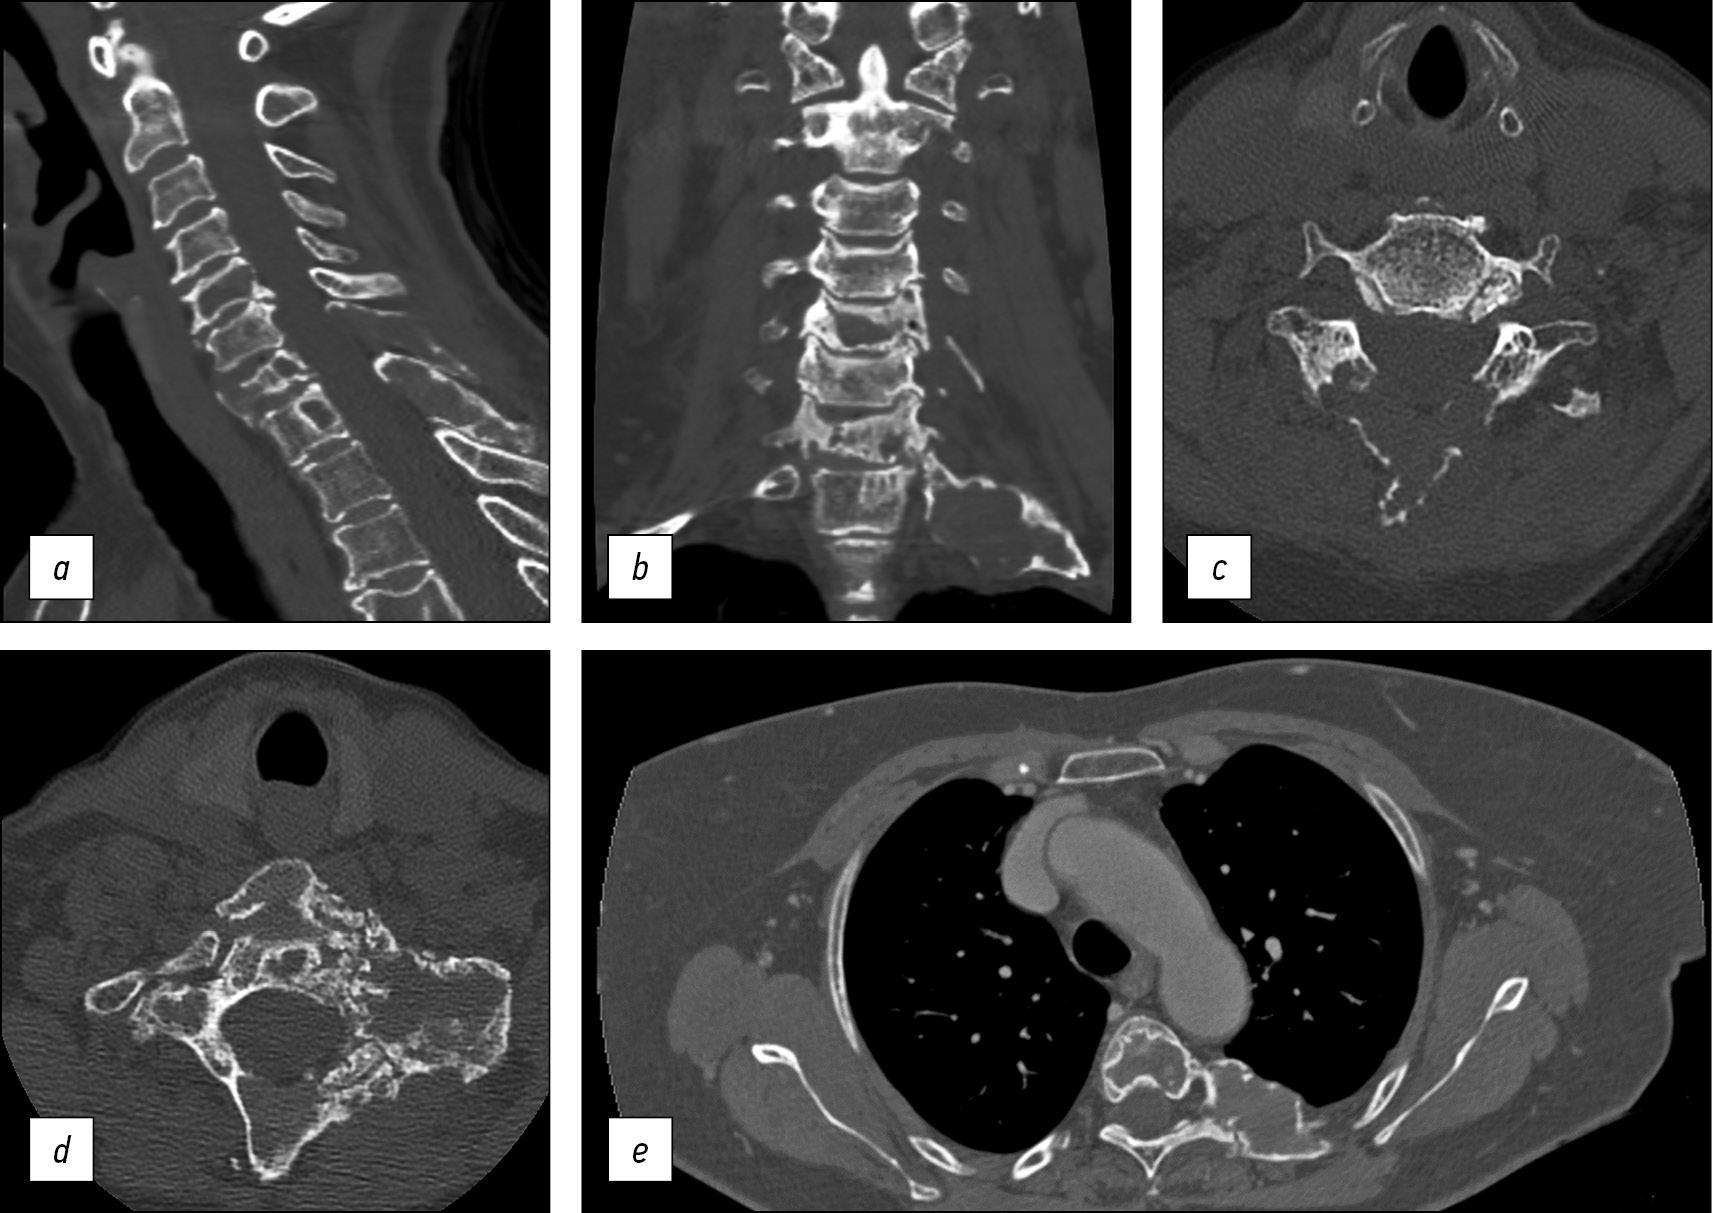

The multiplanar reconstruction CT scan showed a “ground-glass” appearance of the bone matrix, together with homogeneously sclerotic and lytic areas of involved cervical vertebrae, underlying the involvement of C7 and D1 metamers and confirming the C5’s one (Fig. 2a, 2b, and 2c).

The first posterior left rib, already described with a plain radiograph, was better investigated, resulting in the presence of a huge expansile bone lesion with a thin overlying cortical bone and “ground-glass” bone matrix appearance together with cystic lytic areas, which confirm the complete substitution of the trabecular bone with fibrous tissue (Fig. 2d).

Moreover, the total-body CT scan showed the involvement of the fifth dorsal vertebra along the posterior corresponding left rib, which shows the same bony changes as others (Fig. 2e).

Fig. 2. Sagittal (a) and coronal (b) cervical CT showing extensive lytic bone lesions at C5, C7, and D1 vertebrae, involving the seventh cervical posterior laminae and spinous process (c). The posterior arch of the first left rib shows an expansile bone lesion, surrounded by a thin and blown cortical layer, with a ground-glass bone matrix appearance and no soft tissue component (better seen on the axial plane in the figure 2d). Axial plane of the thoracic CT scan showing the involvement of the fifth dorsal vertebra, together with the corresponding left rib (e).